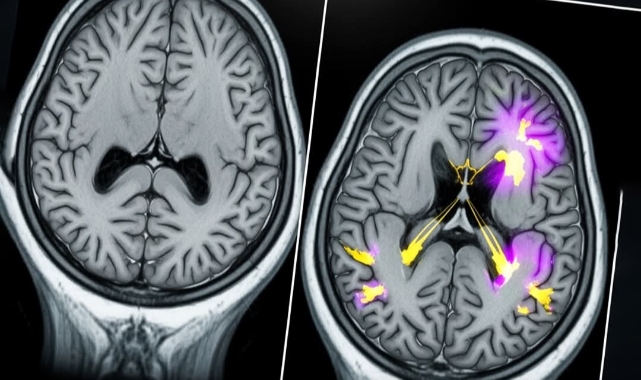

Her şey gencin 17 yaşında hafıza problemleri yaşamaya başlamasıyla başladı. Günlük olayları takip etmekte zorlanıyor, eşyalarını sık sık kaybediyor ve dikkatini toplamakta ciddi problemler yaşıyordu. Bu sorunlar o denli ilerledi ki, genç lise eğitimini tamamlayamadı. Ancak buna rağmen kendi başına yaşamını sürdürebiliyordu.Yapılan beyin taramaları, hafızanın oluşmasında kritik rol oynayan hipokampus bölgesinde küçülme olduğunu gösterdi. Ayrıca omurilik sıvısı üzerindeki biyobelirteç testlerinde klasik Alzheimer işaretleri saptandı. Alzheimer hastalığı genellikle 65 yaş ve üzerindeki bireylerde görülürken, vakaların yaklaşık %10'u daha erken yaşta baş gösteriyor. Ancak 30 yaş altındaki vakaların büyük çoğunluğunda hastalığa genetik mutasyonlar neden oluyor.Bu gencin DNA’sı incelendiğinde ise bilim insanları bilinen genetik mutasyonların hiçbirine rastlamadı. Önceki en genç Alzheimer hastası 21 yaşındaydı ve hastalığına neden olan spesifik bir genetik mutasyon taşıyordu.Araştırmayı yürüten Çinli uzmanlar, bu tür olağan dışı vakaların Alzheimer hastalığının başlangıç süreci ve gelişimiyle ilgili önemli bilgiler sunabileceğini vurguluyor. Bu vaka, Alzheimer'ın yalnızca yaşlıları etkileyen bir hastalık olmadığını çarpıcı şekilde gözler önüne seriyor ve hastalığın nedenlerini anlamaya yönelik araştırmaların ne denli önemli olduğunu bir kez daha hatırlatıyor.

Tıp dünyasını sarsan bir vakayla, Çin'de 19 yaşındaki bir gence Alzheimer teşhisi konuldu. Pekin'deki Başkent Tıp Üniversitesi araştırmacılarına göre, bu genç şimdiye kadar bu hastalıkla teşhis edilen en genç birey olarak kayıtlara geçti.